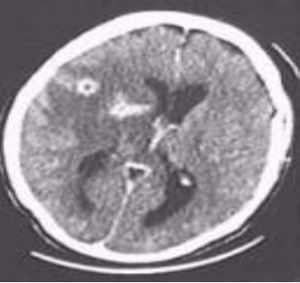

Immagine di TAC encefalo con cisti di toxoplasma gondii

Nei pazienti con sistema immunitario compromesso (persone con infezione da HIV, pazienti affetti da cancro, individui che hanno subito un trapianto, ecc) sono molto più suscettibili all'infezione da Toxoplasma gondii e possono sviluppare sintomi più severi; i sintomi neurologici sono i segni più comuni, encefaliti, mal di testa, disorientamento, spossatezza, deficit motori, epatite con insufficienza epatica, convulsioni, che possono condurre al coma e morte nei casi più gravi. Frequenti Sono le infezioni a carico dell'occhio con cecità e a carico delle vie respiratorie. Il discorso cambia in caso di insorgenza della malattia in gravidanza: in questo caso l'infezione diventa pericolosa se contratta nel primo trimestre, non tanto per la gestante, quanto per il bambino, infatti, il parassita può attraversare la placenta e danneggiare gravemente il feto.

- Soggetti con toxoplasmosi latente con localizzazione cerebrali di cisti di toxoplasma.

La toxoplasmosi è un'infezione frequente, spesso a decorso benigno, ma in alcune categorie di soggetti, donne e persone con deficit del sistema immunitario, può essere pericolosa. In caso di manifestazioni cliniche e diagnosi accertata di toxoplasmosi, è necessario eseguire la terapia antibiotica. Prima della gravidanza eseguire i test per la toxoplasmosi; la donna che contrae l'infezione durante la gravidanza deve essere inviata in centri specializzati. Le buone norme igieniche come il divieto di consumare carni crude, evitare il contatto con animali, sopratutto gatti, prevengono il 41% delle infezioni in gravidanza. In tutti i soggetti, sani e senza patologie psichiatriche che manifestano disturbi del comportamento (aggressività e impulsività), è buona norma clinica, escludere anche eventuali lesioni cerebrali da toxoplasmosi, attraverso esami di laboratorio e radiologici (Risonanza magnetica o TAC cerebrale).